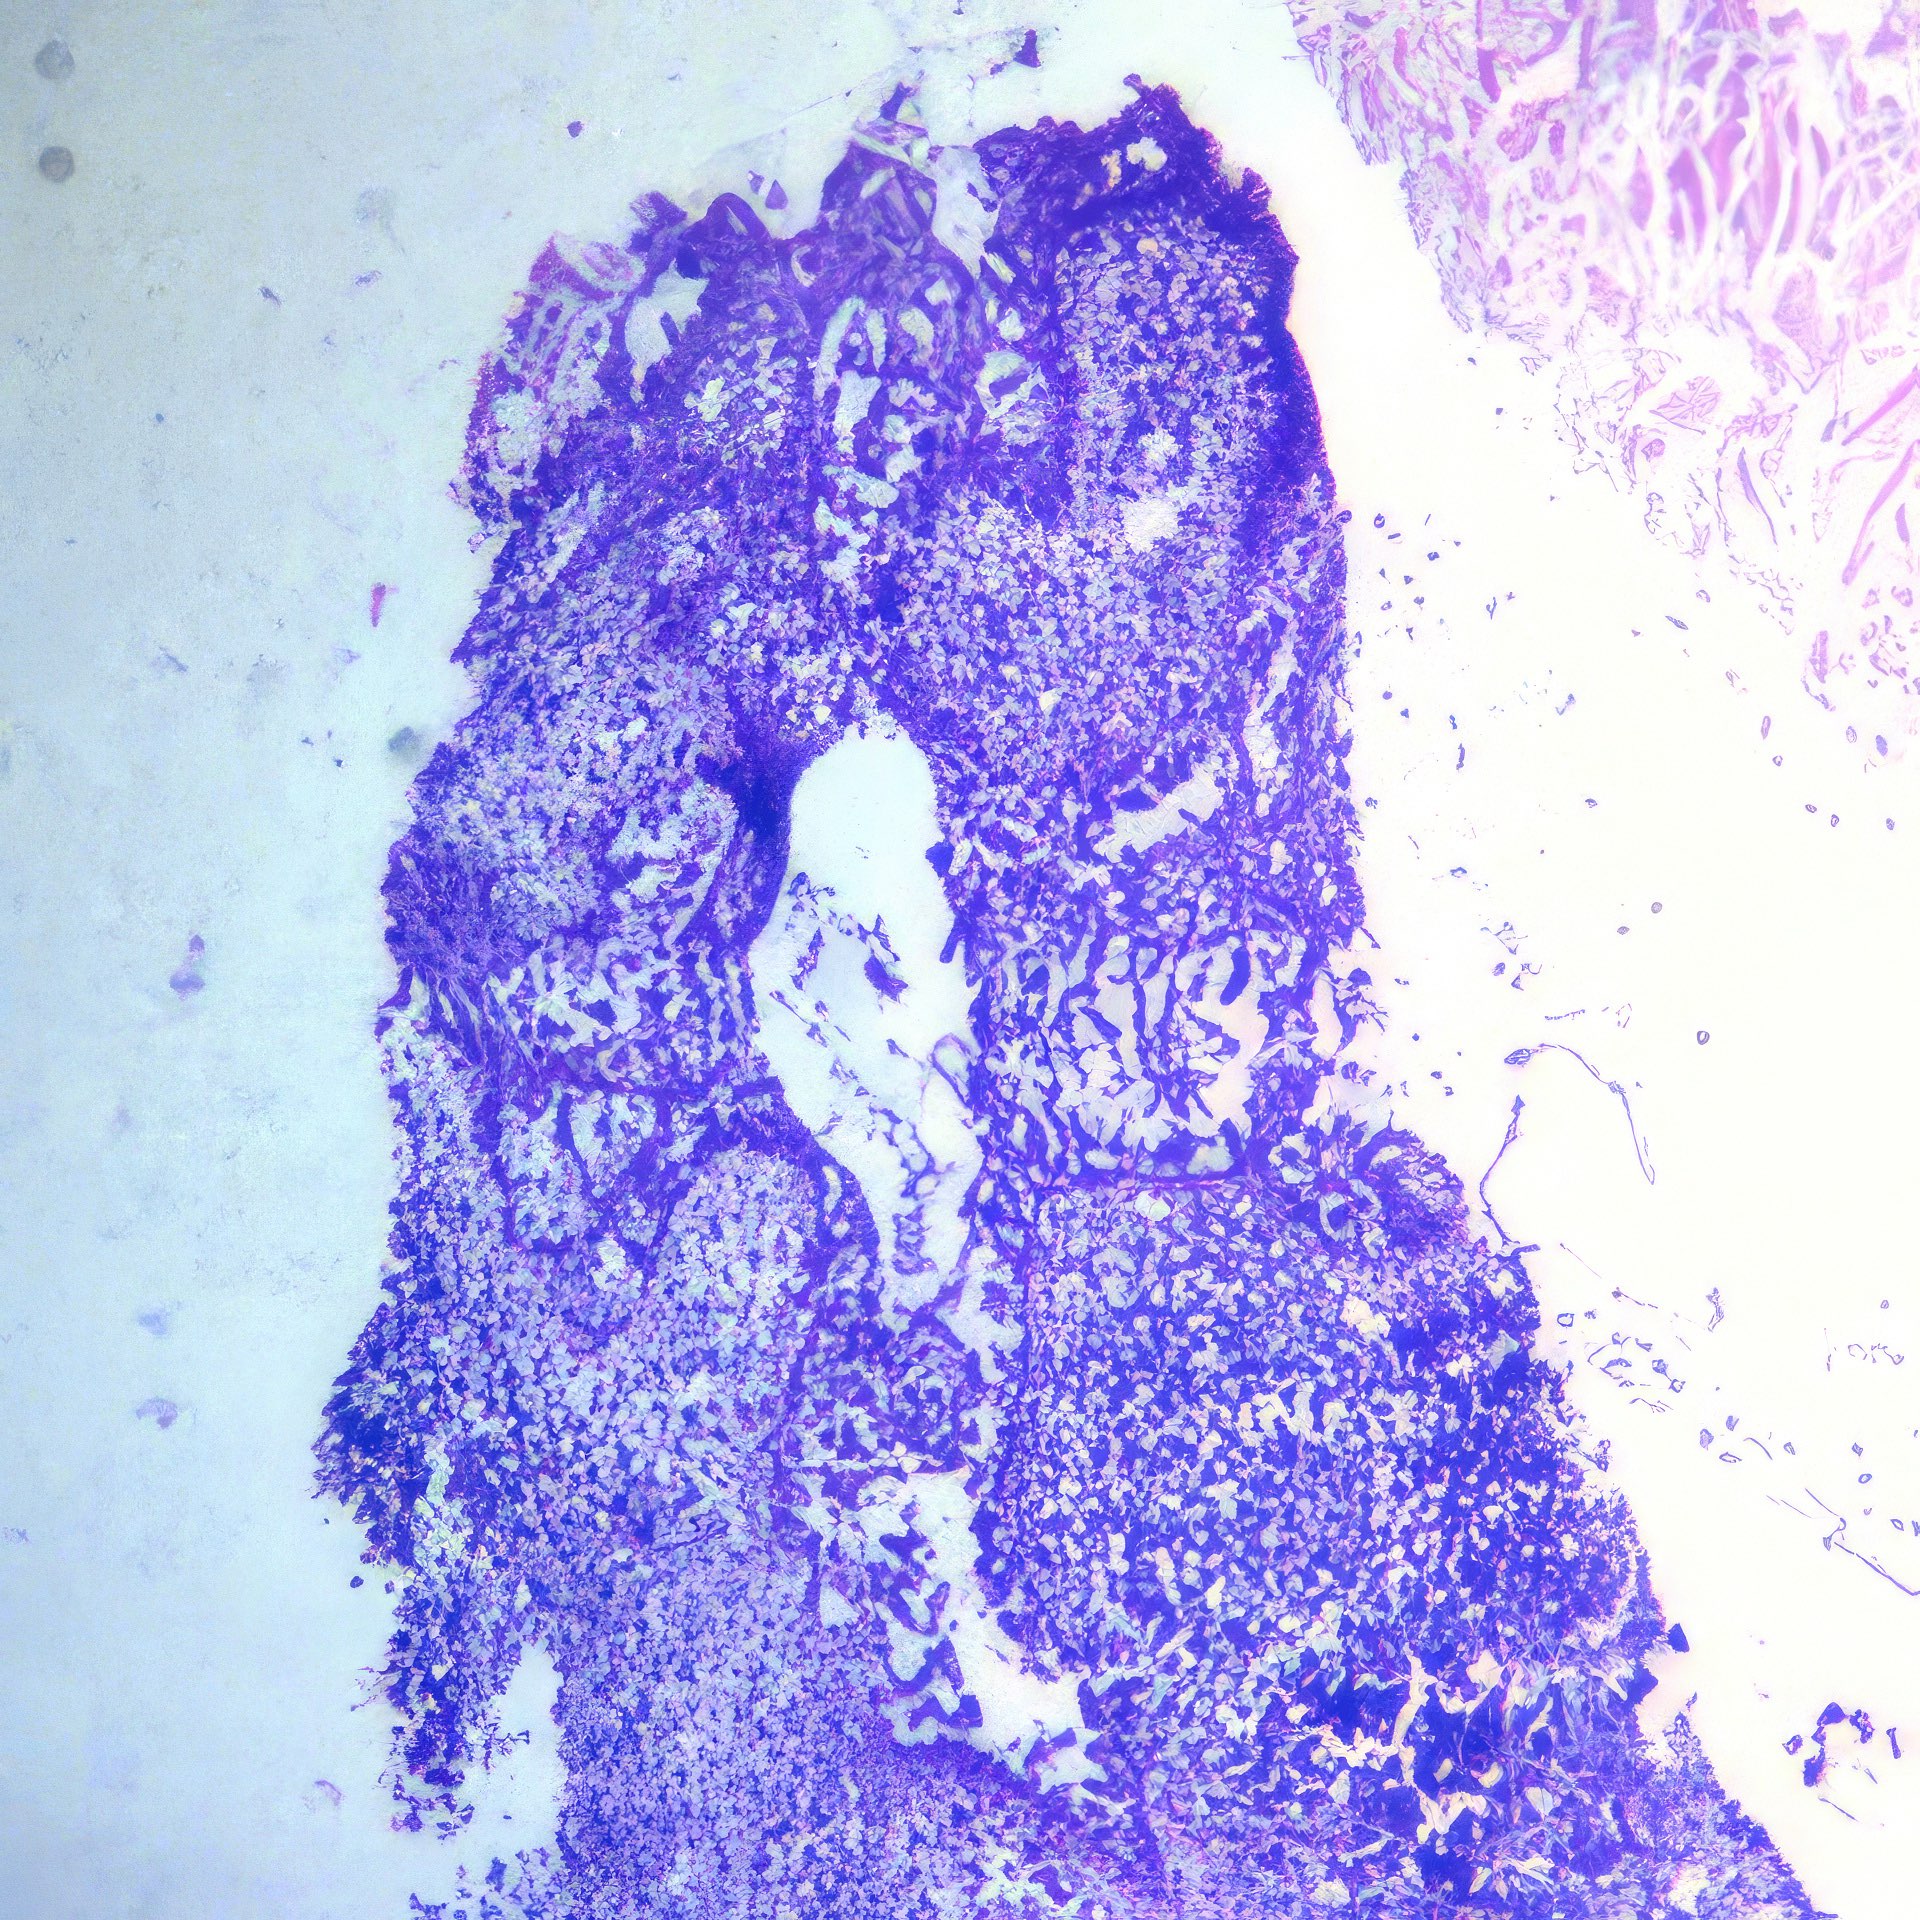

Abbildung 1 – 4: HE-Färbung; 1 – 4, original Obj. 40x, Abb. 4:

zusätzlich vergrößert

Histologie

Die histologischen Bilder (Abb. 1 und 2) bestätigen die zytologische Diagnose. Weite Teile des Gewebes sind durchsetzt von Tumorzellen, die nur angedeutet Verbände bilden und deutlich polymorphe Kerne aufweisen.

In diesem Fall bestand schon bei der klinischen Untersuchung kein Zweifel an der Karzinomdiagnose wegen eingezogener Brustwarze, oranger Hautfärbung und vergrößertem axillärem Lymphknoten, was klinisch nach WHO-Klassifikation T4bN1 entspricht. Die zytologische Diagnose eines Mammakarzinoms ist nicht immer so einfach. Dies gilt vor allem für das gut differenzierte tubuläre Karzinom, bei dem Größe und Form der Zellen nur schwer von normalen Zellen zu unterscheiden sind 12. Ähnliches gilt für das lobuläre Karzinom, dessen Zellkerne auch nur wenig in Form und Größe variieren; das auffälligste zytologische Merkmal ist die auch im zytologischen Präparat teilweise nachweisbare Indianfile-artige Anordnung 3. Die Trefferquote professionell durchgeführter FNA liegt knapp über 90%. Mag auch die Trefferquote der Dicknadel-Biopsie noch um wenige Prozent höher sein 4, so bietet die FNA besonders in unterversorgten Ländern den Vorteil, dass die Herstellung der Präparate einfacher, billiger und weniger zeitaufwendig ist.